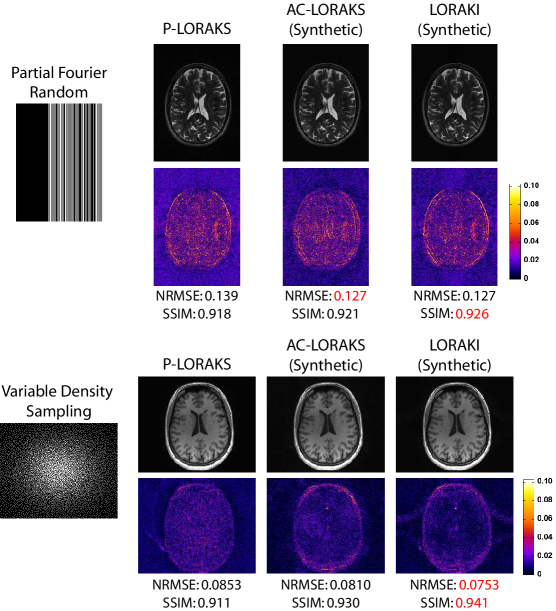

To evaluate the hypothesis that LORAKI would be compatible with a range of different sampling patterns (a characteristic that it should inherit from AC-LORAKS), we performed reconstruction of the T2-weighted data from random undersampling (an effective acceleration factor of 3ร—3\times, including 32 fully-sampled lines of central k-space to be used as ACS data) and partial Fourier undersampling (5/8ths partial Fourier sampling including 32 fully-sampled lines of central k-space to be used as ACS data, with uniform sampling of the remaining k-space resulting in an effective acceleration factor of 3ร—3\times). LORAKI reconstruction results for one slice are shown in Fig.ย 4, and AC-LORAKS results are also included for reference. As can be seen, the advantage of LORAKI over AC-LORAKS is still observed for these sampling patterns, and there is still not a major difference between using the original ACS data and synthetic ACS data.

The results shown in the previous section demonstrated that LORAKI has potential advantages compared to existing AA methods when sufficient ACS data is available, and also that synthetic ACS training data is potentially useful for scenarios where it may be impractical to acquire a large amount of actual ACS data. In practice, there can also be certain scenarios where no ACS training data is available, where existing calibrationless reconstruction methods like SAKE and LORAKS (which are also based on linear autoregressive modeling principles) have previously demonstrated value [8, 9, 19]. While the LORAKI formulation does not directly address calibrationless scenarios, it is worth noting that LORAKI could also potentially be applied to such scenarios if synthetic ACS data can be generated (e.g., by applying a calibrationless reconstruction method as an initial step). As an initial proof-of-principle for this idea, we performed two different calibrationless simulations, as shown in Fig.ย 7. With the T2-weighted data, we simulated calibrationless random partial Fourier undersampling with an effective acceleration factor of 3.5ร—3.5\times. With the T1-weighted data, we simulated calibrationless variable density random sampling with an effective acceleration factor of 5ร—5\times. In both cases, we used the โ€œSโ€-version of the nonconvex P-LORAKS method [19] (using publicly available software [41]) to generate an initial reconstruction. This initial reconstruction was then used as synthetic ACS training data to train LORAKI, and LORAKI reconstruction was then performed. Reconstruction results are shown in Fig.ย 7, and we also show the P-LORAKS reconstructions and AC-LORAKS reconstructions (trained using the P-LORAKS reconstruction as ACS data) for reference. As can be seen, the LORAKI reconstruction frequently has the best performance metrics compared to P-LORAKS and AC-LORAKS. The one exception is that AC-LORAKS has a slightly better NRMSE value for the T2-weighted data, although the difference in NRMSE between LORAKI and AC-LORAKS is nearly negligible in this case (i.e., an NRMSE of 0.1274 for LORAKI versus 0.1271 for AC-LORAKS). These results confirm that LORAKI-type approaches can still have relevance to calibrationless scenarios.

Refer to caption

Figure 4: AC-LORAKS and LORAKI reconstruction results for T2-weighted data with different non-uniform sampling patterns. (top) Random sampling. (bottom) Partial Fourier sampling. Error images are shown using the same colorscale from Fig.ย 2.

Figure 7: Evaluation of calibrationless reconstruction using synthetic ACS data. Error images are shown using the same colorscales from Figs. 2 and 3.